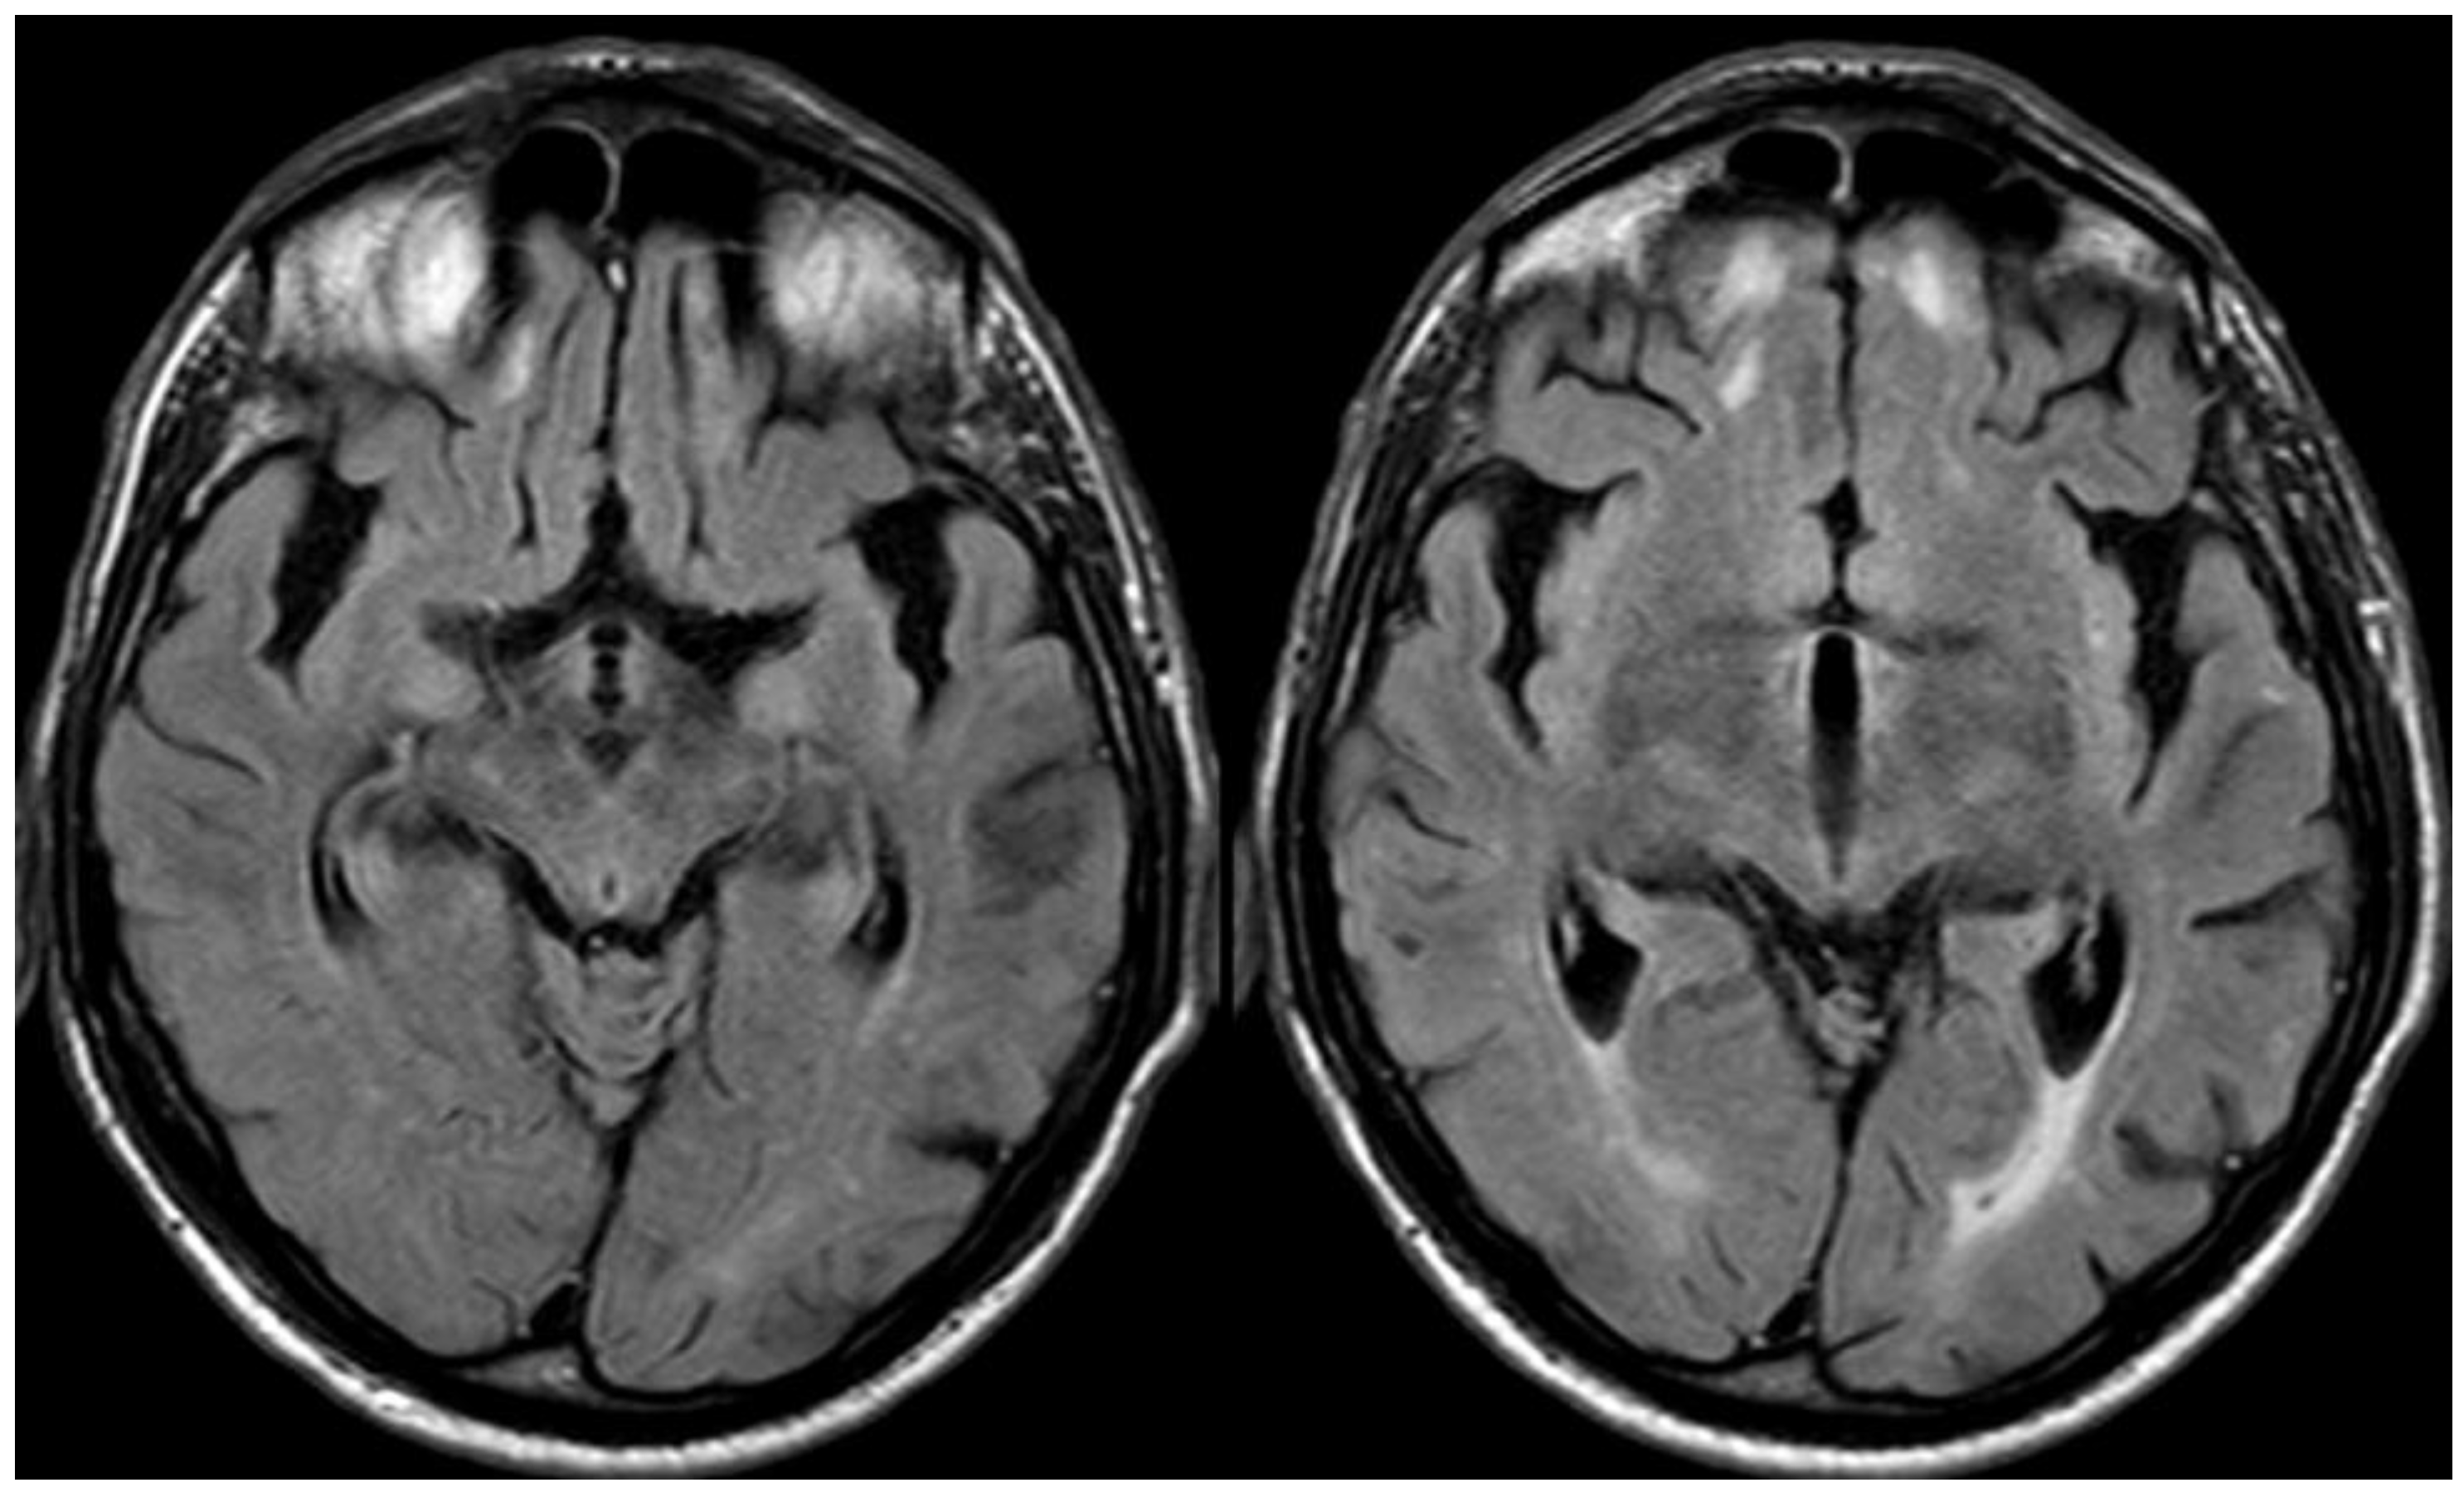

2. December 2013: Sulcal SAH and TFNEs

6. December 2017: Recurrent SAH